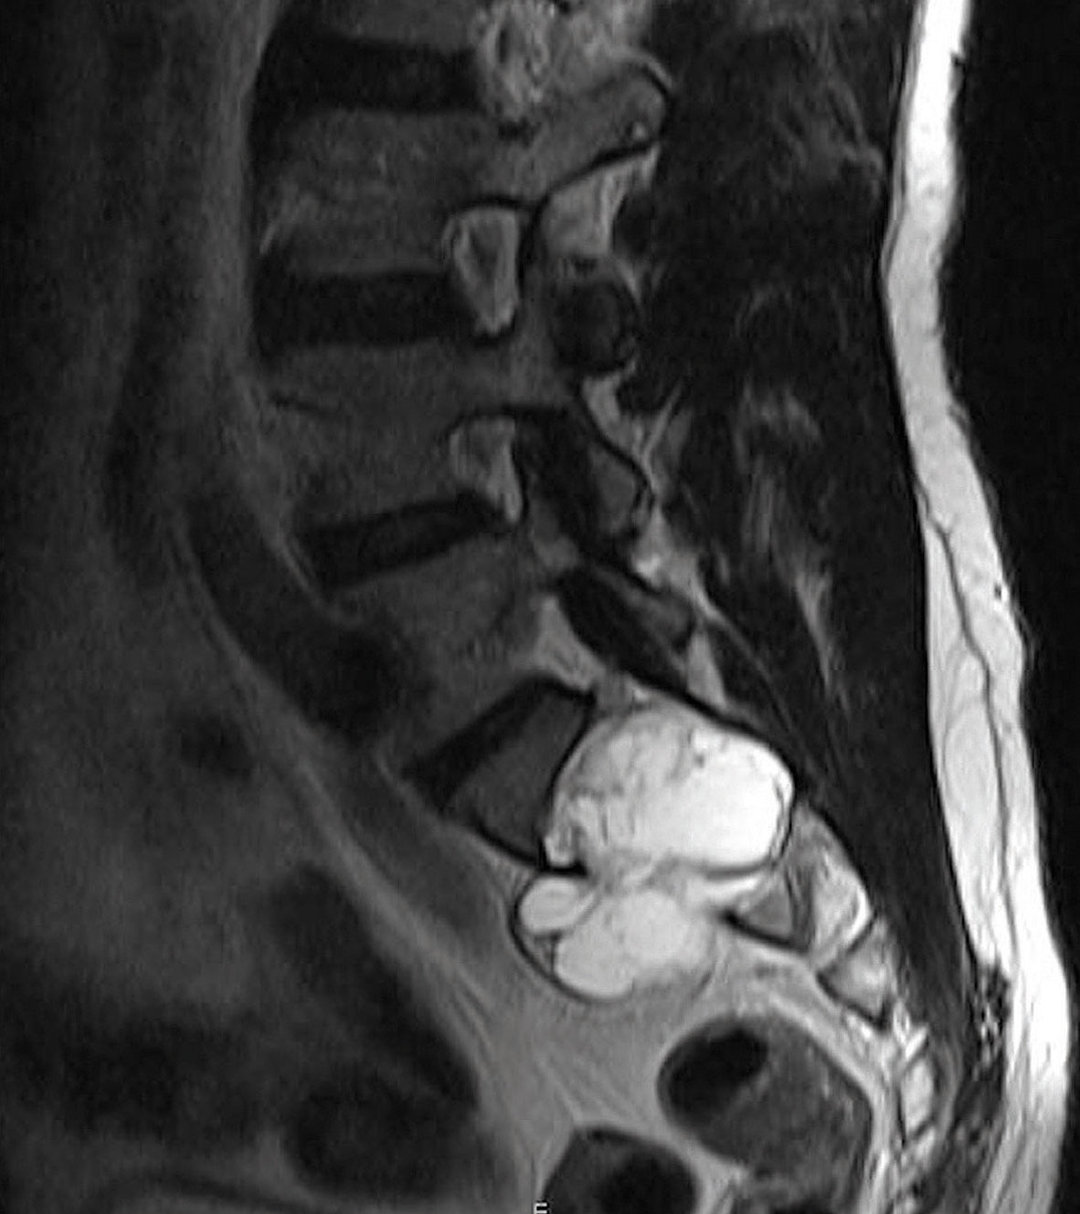

Fall 1

Ein 37-jähriger Soldat konsultiert den Truppenarzt wegen seit einem Jahr bestehender Leistenschmerzen. Die radiologische Diagnostik förderte eine Raumforderung auf Höhe BWK 11 zutage, die auch vom mitbeurteilenden Neurochirurgen als unkomplizierte Zyste ohne Zusammenhang mit den Beschwerden gewertet wurde. Obwohl man in einer erneuten MRT-Untersuchung zwei Jahre später eine Größenzunahme der Läsion feststellte, blieben die Ärzte bei dieser Einschätzung. Dies änderte sich erst, nachdem der Patient vom Truppenarzt ins Bundeswehrkrankenhaus geschickt wurde, um eine Zweitmeinung einzuholen.

„Größenprogredienz, randständige Kontrastmittelaufnahme sowie eine zwischenzeitlich aufgetretene Gang­unsicherheit schienen nicht für eine unkomplizierte Zyste, sondern vielmehr für einen rückenmarkkomprimierenden zystischen Tumor zu sprechen“, schreiben Dr. Schulz und seine Kollegen. Intra­operativ stellte sich der Befund als Schwannom heraus, das vollständig entfernt werden konnte. Schmerz und Ganganomalie wurden durch den Eingriff beseitigt.